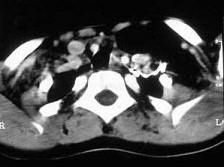

问题 女,17岁,发现左侧颈部包块半年余,PE:病灶质软,境界不清,无压痛,CT如图所示,应诊断为()

选项 A.颈部脂肪瘤 B.颈部畸胎瘤 C.颈部错构瘤 D.颈部淋巴管瘤 E.颈部陈旧性血肿

答案 A